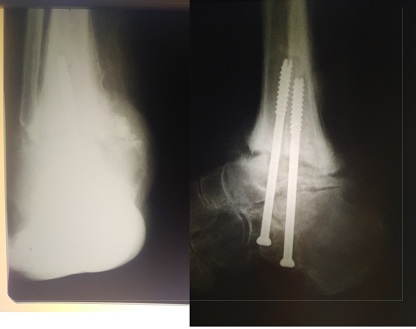

Диабетическая нейроостеоартропатия (ДНОАП) - одно из самых тяжелых осложнений сахарного диабета, требующее сотрудничества ряда специалистов, в том числе травматологов-ортопедов. Однако отсутствует единый подход в выборе тактики ортопедического лечения данной группы пациентов. С 2015 по 2018 гг. включительно наблюдались 35 пациентов с ДНОАП, которые получали консервативное или оперативное ортопедическое лечение. 11 пациентов получали консервативное ортопедическое лечение, хирургическое лечение получили 24 пациента. Всего выполнено 26 оперативных вмешательств. Выполнялось два типа хирургических вмешательств: 1) резекция выступающего фрагмента той или иной кости предплюсны - 12 операций; 2) реконструктивная операция, направленная на коррекцию грубой деформации среднего и/или заднего отдела стопы, - 14 операций. Наряду с общеклиническим обследованием всем пациентам проводились ортопедическое обследование, определение степени нарушения кровоснабжения. Дифференцированный подход к выбору метода ортопедического лечения представленной группы пациентов позволил восстановить опороспособность конечности, обеспечить стабильность в голеностопном суставе и суставах среднего отдела стопы, создать условия для заживления и предотвращения рецидива язвы. Полученный опыт позволил предложить показания для того или иного метода ортопедического лечения деформаций стоп при ДНОАП в зависимости от стадии патологического процесса, его локализации, степени выраженности деформации и клинического течения данной патологии.